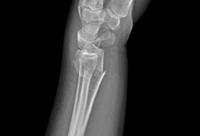

Wrist fractures

Type B (simple) intra-articular fracture of the distal radius: lateral view

From the collection of Dr Chaitanya S. Mudgal